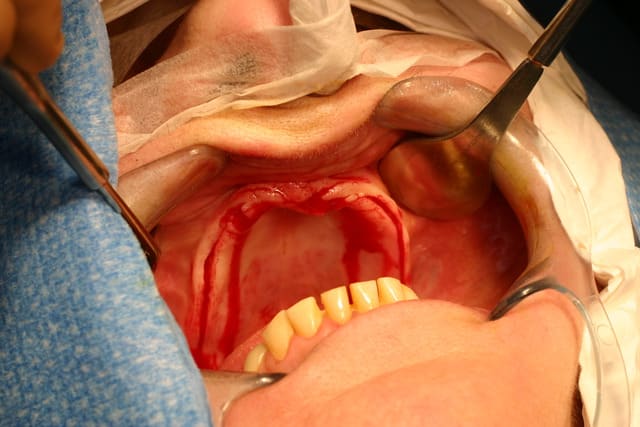

Je vais te filer qques photos d une patiente opérée voici 3 ans avec du nano et des plaques rien que l aspect de la muqueuse te montrera que tout ça est sain et ossifié

Merci, je me souviens bien de ce cas déjà présenté.

Le volume est en effet bien plus grand après, mais je me permet d'avoir quelques doutes sur l'intégration des plaques au niveau osseux...reste à avoir des études et des statistiques sur quelques centaines de cas, voir plus ;-)